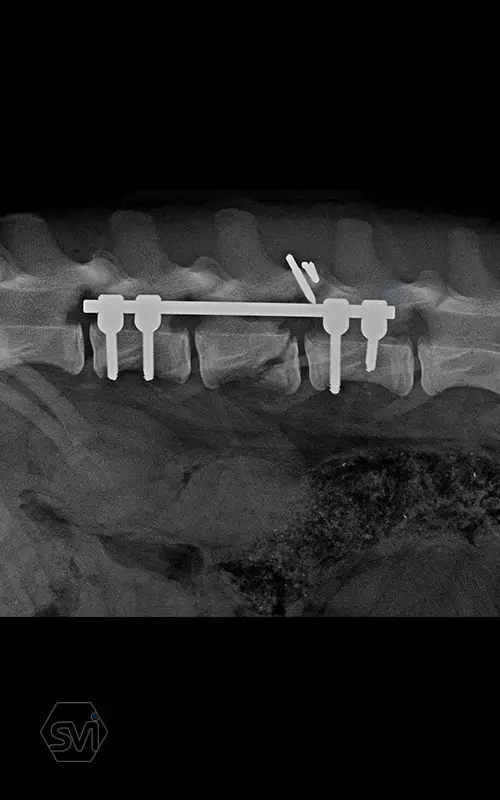

Kutya neve: Benetton, az SOP-LC hatékonysága és stabilitása magáért beszél, a gyógyulás alatt a gerinc folyamatos terhelés alatt volt, és a fémek nem mozdultak el. A kutya szerencsére neurológiailag i felépült! Tehát van esély a gerinctörések esetén is a gyógyulásra...